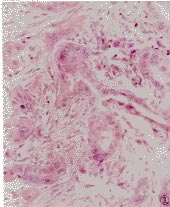

混合性結締組織病--潰瘍性病變手部瀰漫性浮腫(66%)伴有指端變細或成梭形手指,手部腫脹的病例局部皮膚緊張而肥厚,似臘腸樣。組織病理檢查顯示膠原組織增生,這種硬皮病樣的表現有時較為廣泛,但呈瀰漫性者相對少見。毛細血管擴張常見,多見於面部和甲皺襞上部,但一般不發生壞死性及潰瘍性病變。在暴露部位常可見到類似紅斑狼瘡樣皮損,亦可見SLE樣蝶形紅斑,以及像皮肌炎所見的手指關節背面的萎縮性紅斑性皮疹及眼瞼紫紅色水腫等。

混合性結締組織病--臨床表現肌肉病變呈近端肌肉疼痛、壓痛和無力,占60%-75%,血清肌漿酶如肌酸磷酸激酶、醛縮酶、乳酸脫氫酶和穀草轉氨酶可升高,尿肌酸排出正常或升高,肌電圖異常,肌肉活檢呈局灶性炎症性肌炎,間質和血管周圍淋巴細胞和漿細胞浸潤,肌纖維退行性變。關節病變呈多發性關節炎或關節痛,占87%-100%,關節畸形少見,有時偶見如類風濕性關節炎的畸形。肺病變約占70%,有些臨床上可無呼吸道症狀,有暫時性胸膜炎,可伴少量胸腔積液,間質纖維化,肺功能測定3/4病例受損,最常見為一氧化碳彌散功能障礙和肺活量減低,呼吸受限,某些有運動性呼吸困難和肺動脈高壓,後者可繼發於肺纖維化或肺小動脈內膜增生。X線攝片可見肺基底部網狀結節陰影、變換位置的肺實質變化。心臟病變約30%有心包炎,尚可有心肌炎、完全性傳導阻滯、節律紊亂和心力衰竭,亦可有瓣膜病變如二尖瓣閉鎖不全和狹窄,曾報導一例主動脈瓣閉鎖不全引起心力衰竭。腎臟累及少,約5%-25%,腎穿刺示瀰漫性膜性增生性改變、瀰漫性膜性腎炎、局灶性腎小球腎炎、腎小球血管膜細胞增生、細胞浸潤、內膜增殖和血管閉塞。